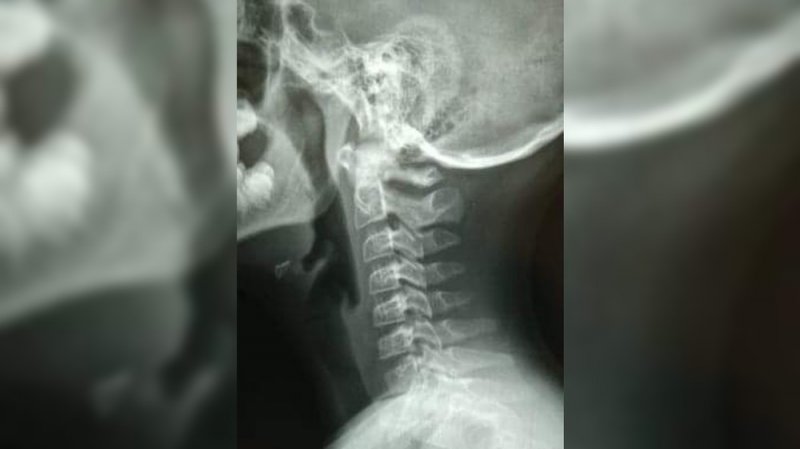

“Mi hijo tiene lastimado el cuello y rasguños en la cara […] tampoco puede pasar alimentos, por lo cual hago responsable al docente Marco Antonio Reveles Herrera”, denunció la mamá en Twitter.